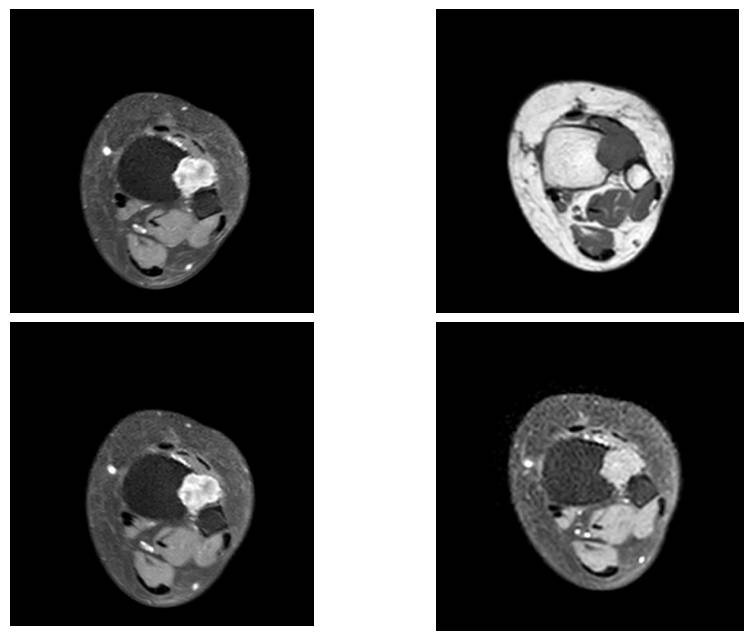

Before the surgery: The MRI shows an irregularly bordered, heterogeneous mass causing bone destruction in the same location.